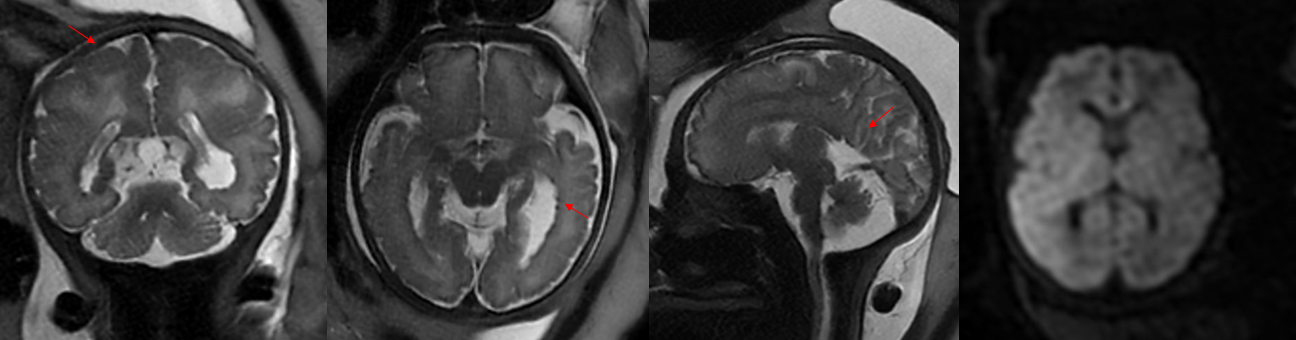

“经济负担倒是次要的,最主要是人的精神压力。你想一想,家里有个生病的孩子,可能需要陪他到处去看病治疗,一辈子离不开人照顾,对整个家庭会造成多么大的负担。” 湖北省妇幼医学影像科杨文忠主任解释出生缺陷家庭所背负的重担。